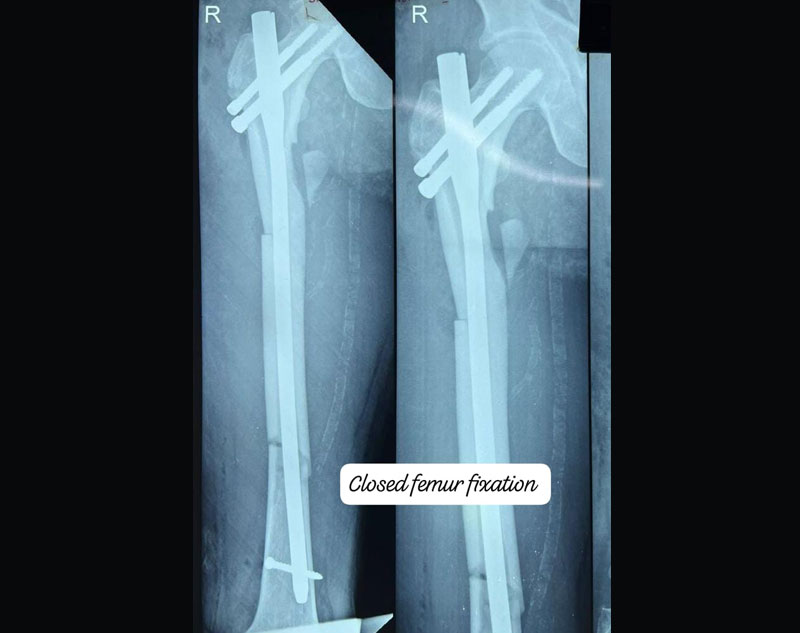

Treatment for complex trauma requires a multidisciplinary approach, including surgical intervention, internal/external fixation, and sometimes reconstruction of damaged tissues.